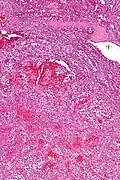

| Low magnification micrograph of a littoral cell angioma. H&E stain. | |

Littoral cell angiomas show in CT scans. They are diagnosed by pathologists by taking a sample of the tumour via Fine Needle Aspiration or Core Needle Aspiration or from a splenectomy. Histologically, they have anastoming small vascular channels and cystic spaces with papillary projections.[2]